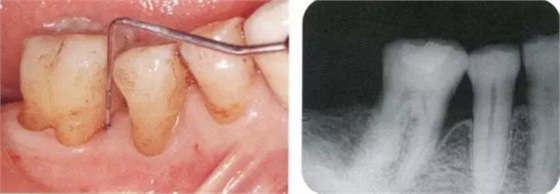

▲圖17-1,2

▲圖17-1 下頜右側磨牙區(qū)的邊緣嵴高度不齊,右下6近中有6mm的牙周袋。在這種邊緣嵴存在高低差的情況下,很容易引發(fā)食物嵌塞。

▲圖17-2 同部位的X光片。右下6近中有牙槽骨緣下牙周袋。